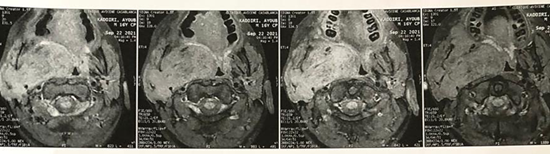

Inwardly and inferiorly, it infuses the hypopharynx

and the proximal part of the larynx, which remain permeable (Figure 5). Downwards and outwards, it

infiltrates the right submandibular gland and the base of the tongue (Figure 5).

Figure 5: MRI on axial section

showing the infiltration of the base the tongue and the hypopharynx

Figure 6: MRI on axial section

showing the infiltration of the right maxillary sinus.